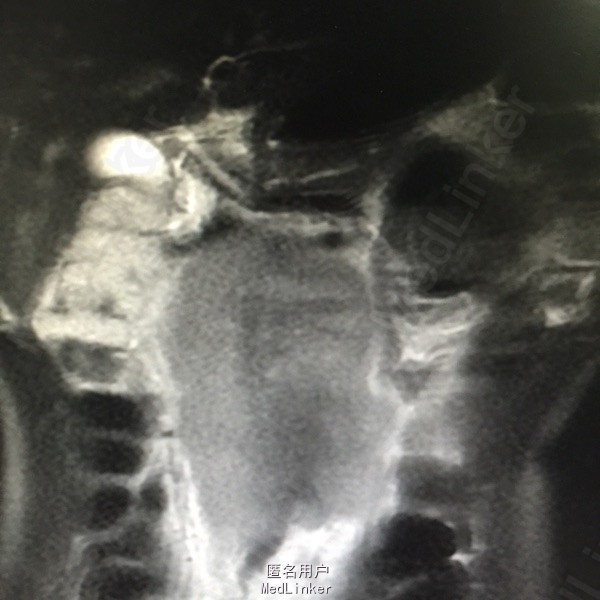

查体:上腹少许压痛,中腹部可门机一大小约8*8cm的肿物,质地硬,活动性差,无明显按压痛。其余无特殊。 辅助检查:腹部MR:1.腹膜后占位(80*92*147cm),考虑淋巴瘤可能性大,病灶推压下腔静脉、门静脉主干及胰腺,包绕腹主动脉、肠系膜上动脉、双侧髂血管及双侧肾动脉,双侧肾静脉显示不清。2.肝左叶内胆管轻度扩张。胃镜示:1.慢性浅表性胃窦炎,2.胃窦粘膜隆起待查:异位胰腺?B超引导下行肿物穿刺活检术,病理结果示:符合生殖细胞来源恶性肿瘤,考虑精原细胞瘤可能性大。后完善盆腔CT示:1.右侧睾丸肿物,性质为恶性肿瘤,考虑为精原细胞瘤可能,阴囊右侧积液,腹膜后、肠系膜根部、盆腔内多发淋巴结转移,不除外累及胰头、体部、右侧腰大肌可能,下腔静脉、双侧髂总、内静脉、右髂外静脉、股静脉腔广泛栓子形成;盆腔少量积液。

诊断考虑精原细胞瘤。予全麻下右侧睾丸切除术,术后予BEP方案化疗,并予抗血小板治疗。

患者3程化疗后复查CT评估PR:腹膜后大血管周围、盆腔内可见多发肿大淋巴结影,部分融合成团,最大层面范围为52*29cm,较前明显缩小。 精原细胞瘤起源于睾丸原始生殖细胞,为睾丸最常见的肿瘤,多发生于中年以后,常为单侧性,右侧略多于左侧。发生于隐睾的机率较正常位睾丸高几十倍。该瘤为低度恶性。高剂量强度的BEP方案(博来霉素+依托泊苷+顺铂)仍是低危生殖细胞肿瘤的最佳治疗方案。